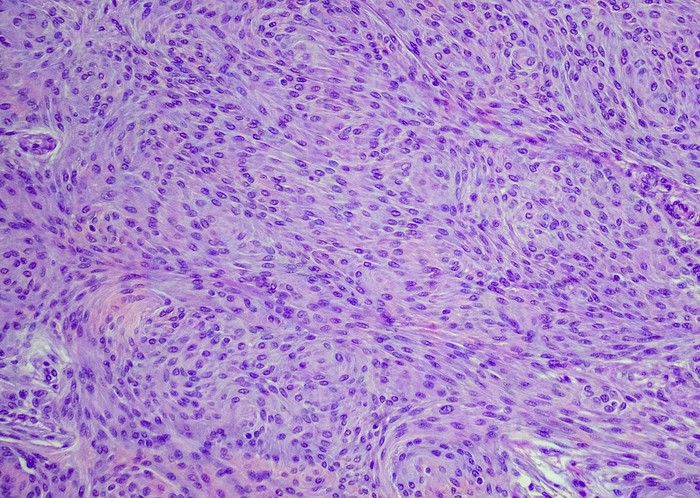

Brain or spinal cord tumors called meningiomas can cause visual impairment, which is sometimes severe and permanent, that can be used as a surrogate for analyzing tumor growth.

Featured photo at top of meningioma cells. Photo/OGphoto/iStock.